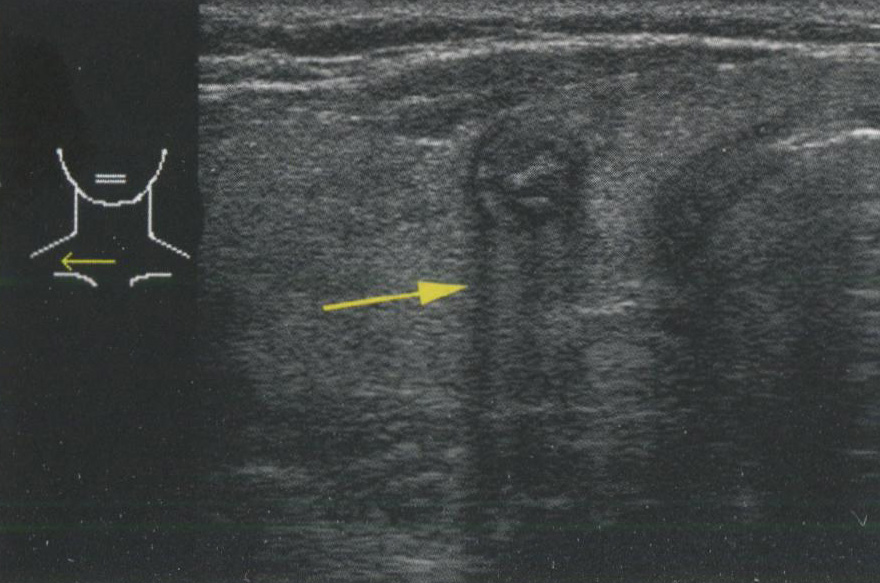

Когда звуковые волны попадают на область с сильно выраженной разницей акустического импеданса, например, на границу ткань-воздух или на кальцинат, подавляющее большинство звуковых волн отражается, обеспечивая очень яркий сигнал, исходящий от поверхности объекта, и отсутствие изображения за его пределами. Рис. 2.9 демонстрирует акустическую тень за кальцинированным узлом. На рис. 2.10 изображен грубый кальцинат в паренхиме щитовидной железы (ЩЖ) с акустической тенью позади кальцината. Рис. 2.11 показывает типичную картину

Рис. 2.9. Акустическая тень. Когда звуковые волны попадают на область с выраженной разницей акустического импеданса, например, на границу ткань-воздух или на кальцинат, подавляющее большинство звуковых волн отражается с возникновением тени кзади от исследуемой структуры. Этот кальцинированный узел наблюдался у пациента с семейной формой папиллярного рака трахеи при УЗИ. Поскольку звук через воздух не проводится, изображение задних структур трахеи отсутствует.